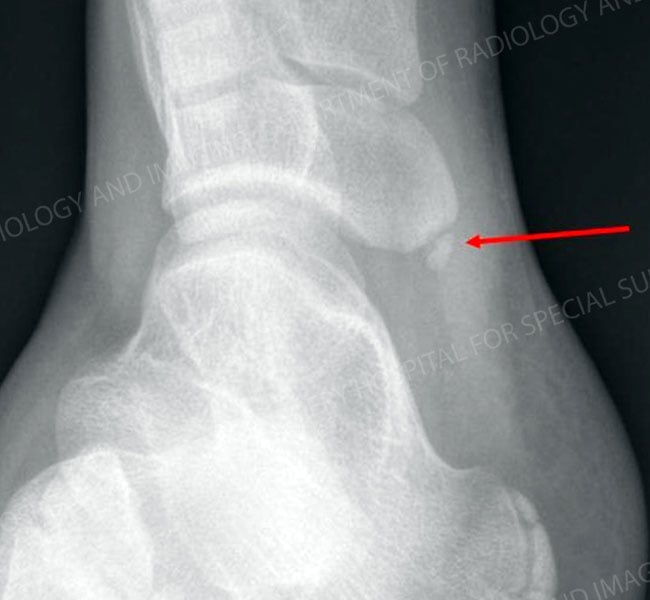

Most tarsal coalitions may be classified as one of two types: a calcaneonavicular coalition, in which the tissue develops between the calcaneus (heel bone) and the navicular (one of the foot bones), or a talocalcaneal or subtalar coalition, in which the coalition develops between the calcaneus and the talus (the ankle bone). The coalition may be composed exclusively of bone, a combination of bone and cartilage, or even fibrous tissue. Tarsal coalitions occur in both feet in about half of all cases.

Right foot with calcaneonavicular coalition. The red arrow indicates the coalition.

Initial treatment for tarsal coalitions is non-operative; the patient is required to rest or immobilize the foot. Although pain relief can be achieved in this way, in many cases the result is only temporary. Non-operative treatment can be appropriate for patients with tarsal coalitions that are symptom-free, and whose condition only becomes apparent on x-ray taken incidentally for another condition, such as an acute ankle sprain.